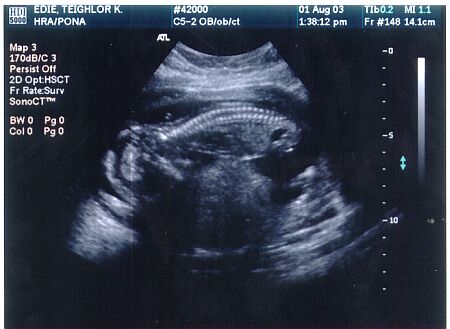

8 1/2 week ultrasound - The baby is head down, facing left you can see the arm and leg buds, butt is up in the air. The fetal heart rate was 176 bpm.